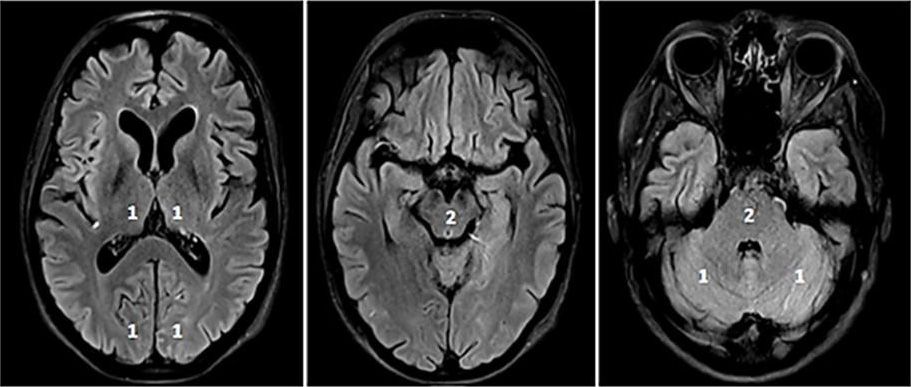

Fig. 4.Modified Thrombolysis in Cerebral Infarction (mTICI) grading system for evaluating the therapeutic success of IVT. No perfusion of the right MCA - mTICI 0 (A). Antegrade reperfusion past the initial occlusion with only filling of a temporal branch of the right MCA - mTICI 1 (B). Antegrade reperfusion of only the superior division of the right MCA - mTICI 2a (C). Antegrade reperfusion of more than half of the previously occluded right MCA territory with persistent filling defect parieto-occipital - mTICI 2b (D). Near complete perfusion except for some distal emboli in several distal cortical vessels frontal and occipital - mTICI 2c (E). Complete antegrade reperfusion of the previously occluded right MCA - mTICI 3 (F).